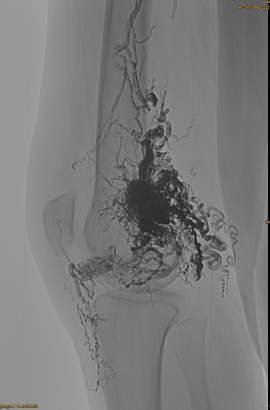

Cov Lus Qhia Yooj Yim ntawm Tus Neeg Mob: Poj Niam, 36 xyoo; Avm pelvis, ntsag, lub hauv caug, sab laug osg, ntau yam ua ntej {1} {1} {{1} {{1} {}} embolizations.

Cov khoom siv siv: 3pcs lava-34,14pcs lava-18.

Ua ntej, txheej thaum ub ntawm istyx los ntawm pre - apholization:

Thawj zaug DSA:

Qhov Kawg:

Sij hawm qeeb, lwm qhov tsim nyog embo, tab sis ntau zoo dua: